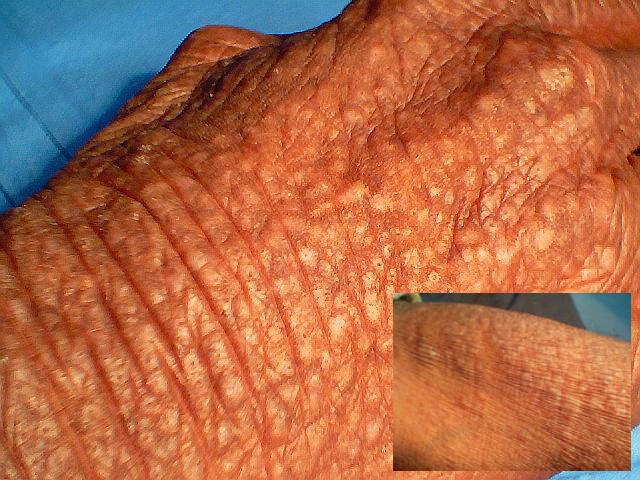

Lichen amyloidosis = الحزاز النشواني

lichen amyloidosus